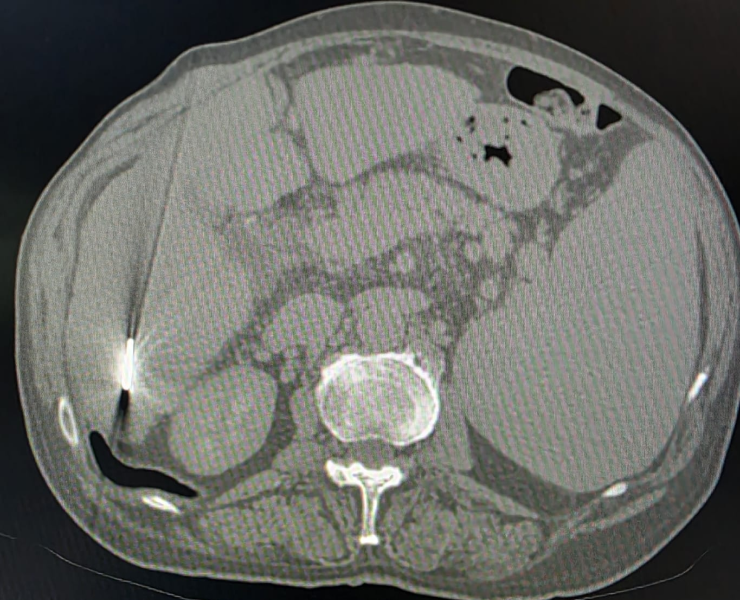

Post treatment (TACE) procedure

Before treatment liver cancer

After treatment of liver cancer

After treatment